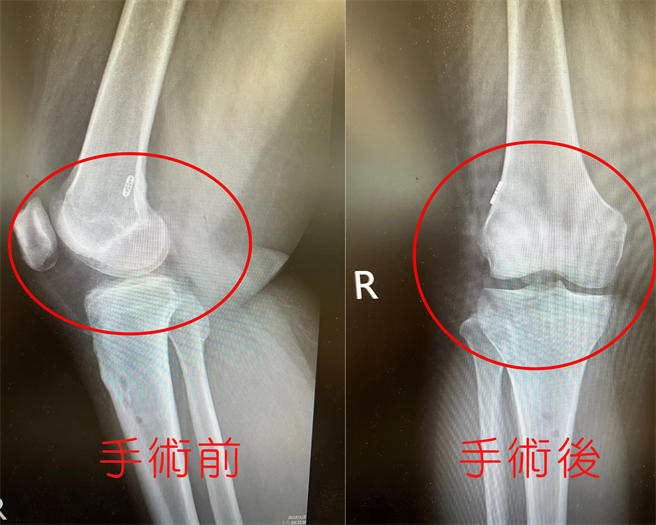

前十字韧带重建手术前后对照图。(亚大医院提供/卢金足台中传真)

蔡孟学指出,前十字韧带断裂就像是被扯断的麻绳松散,膝关节内关节腔的血会渗到周围,没有血肿也不会癒合,必须透过手术的方式进行治疗,一般可透过膝关节镜手术重建十字韧带,可减缓疼痛、增加膝盖稳定度、强化运动功能及避免早期关节退化。

蔡孟学说,韧带重建是指取一段新的韧带,透过关节镜将新的韧带「种」在适当的位置,以取代原本受伤的十字韧带,至于手术后膝关节功能恢復的状况,取决于新韧带的选择、单股或双股重建、取代位置等因素,透过十字韧带重建搭配前外侧韧带固定,将可提供更高的稳定度,特别是旋转的强度,让术后恢復的功能更佳。